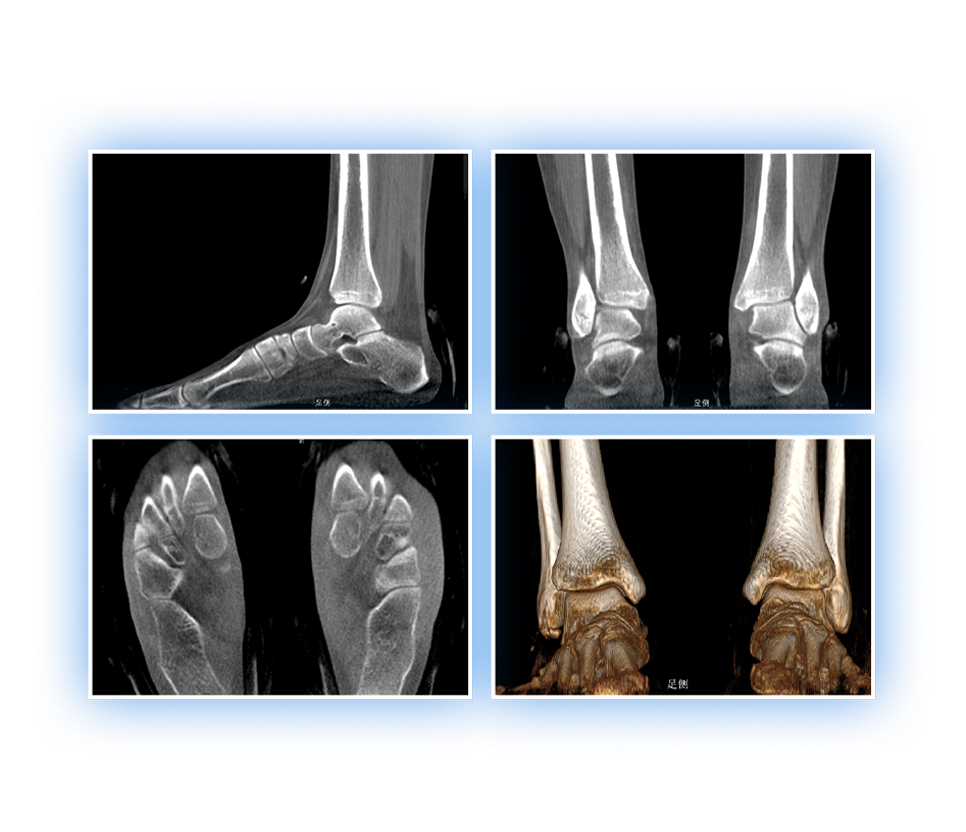

足踝

VR體繪制重建